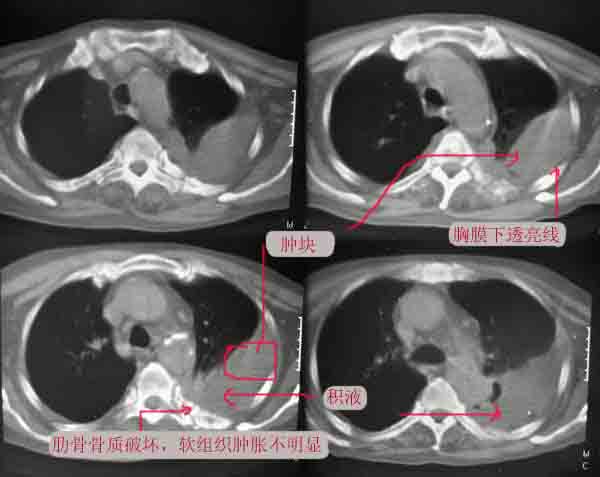

长年偏瘫卧床的病人,73岁,男。最近不能自理,饮食差,知觉不敏感,bp:140/80。脑ct是脑动脉硬化的表现,陈旧多发脑梗死。听诊左肺呼吸音低。行胸部ct扫描发现左侧大量胸腔积液,左侧肋骨虫蚀样破坏,请给予会诊一下:是否转移性病变还是其他?谢谢!

左侧后肋骨及椎弓骨质破坏,考虑转移瘤.降主动脉旁见一软组织块影,肿瘤与压迫之不张肺组织不能鉴别,建议增强扫描.

考虑肋骨骨质破坏,病变肋骨皮质不连续,呈融骨样改变,不象骨质损伤后的修复样改变,未见到明显骨痂显示.软组织肿胀不明显,所以不太支持感染性破坏改变.

左肺上叶尖后段实变、体积缩小,支气管开口后方似有一肿块,与胸壁、主动脉分界不清,局部肋骨呈混合型破坏,考虑肺癌肋骨、胸膜转移。

以下是引用逸风在2006-6-11 16:35:00的发言:[br][br]考虑;左侧周围性肺癌侵犯胸膜并肋骨转移.[br]考虑肋骨骨质破坏,病变肋骨皮质不连续,呈融骨样改变,不象骨质损伤后的修复样改变,未见到明显骨痂显示.软组织肿胀不明显,所以不太支持感染性破坏改变.

在短短的一个月的时间,胸椎变化这么大,如果说不是恶性,那骨质疏松不会这么快吧!(原来的资料因t8、9没变化,所以没有显示)。请注意我现在发的帖子是以t8、9椎体为住的。